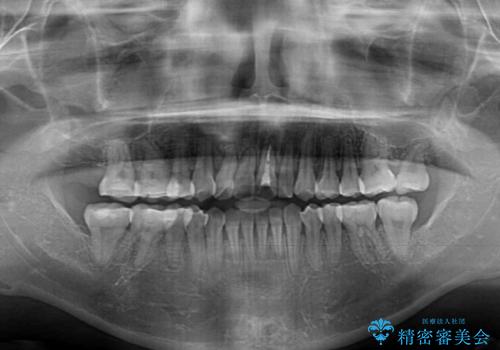

狭い上顎骨を拡大 著しい叢生を抜歯矯正で改善

治療途中、長期間海外旅行をされたり、帰国後には遠方へ転居されたりと、治療期間が伸びましたが、2年強で治療を終えることができました。